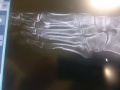

Diagnoza: wielowarstwowe złamanie w lewej stopie. Justyna Kowalczyk komentuje: walczę dalej!

Polska biegaczka walczy z bólem od trzech tygodni. Wszyscy kibice widzieli na jej portalu facebookowym zdjęcie spuchniętej, zasinionej lewej stopy. Kowalczyk starała się nie mówić później na ten temat, podkreślając, że jest na igrzyskach i w Soczi interesuje ją tylko walka o medale.